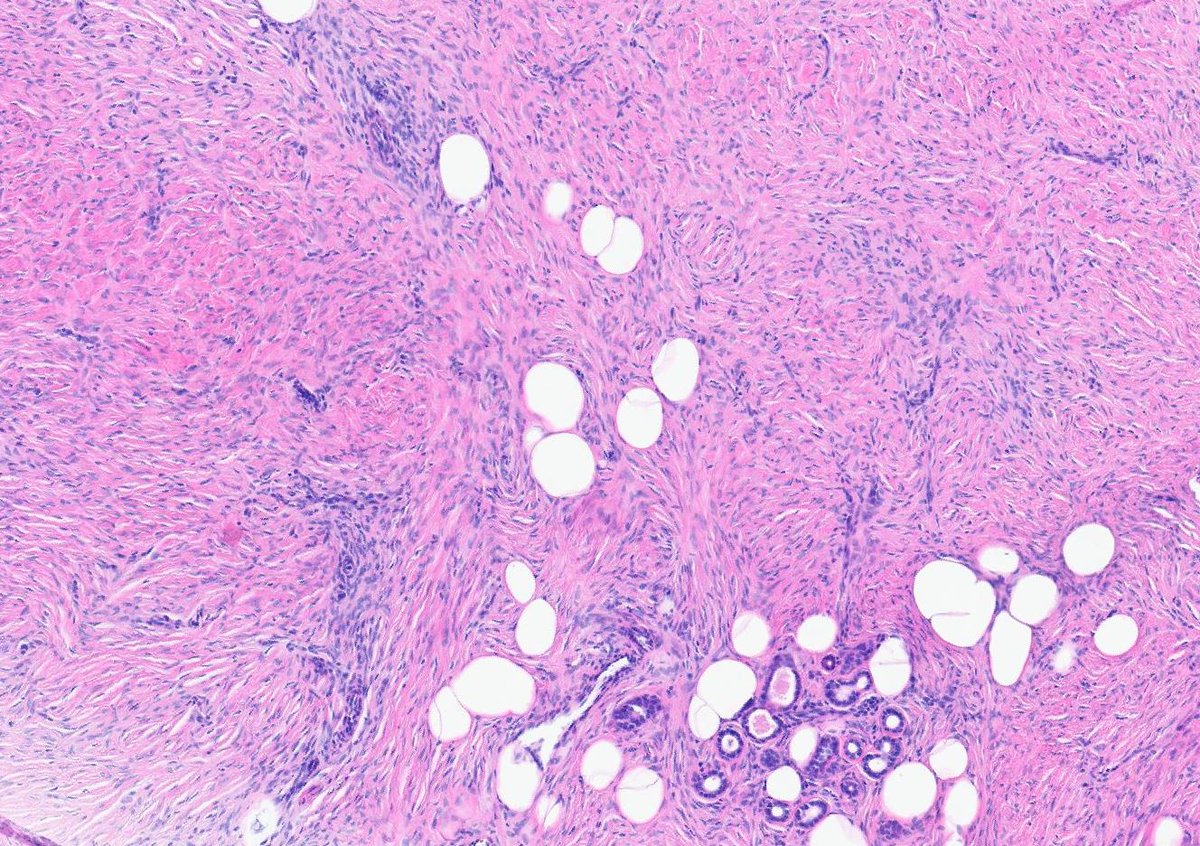

#dermpath 62 yo Man upper back. You worried about this โ€œnevusโ€ ? @david_terrano @et565 @DrGeeONE @SGottesmanMD @kis_lorand @HoustonArsenal @Dr_Jukic @glinglerimek @pembeoltulu @gonzadetoro stains are SOX10 and P16โ€ฆ